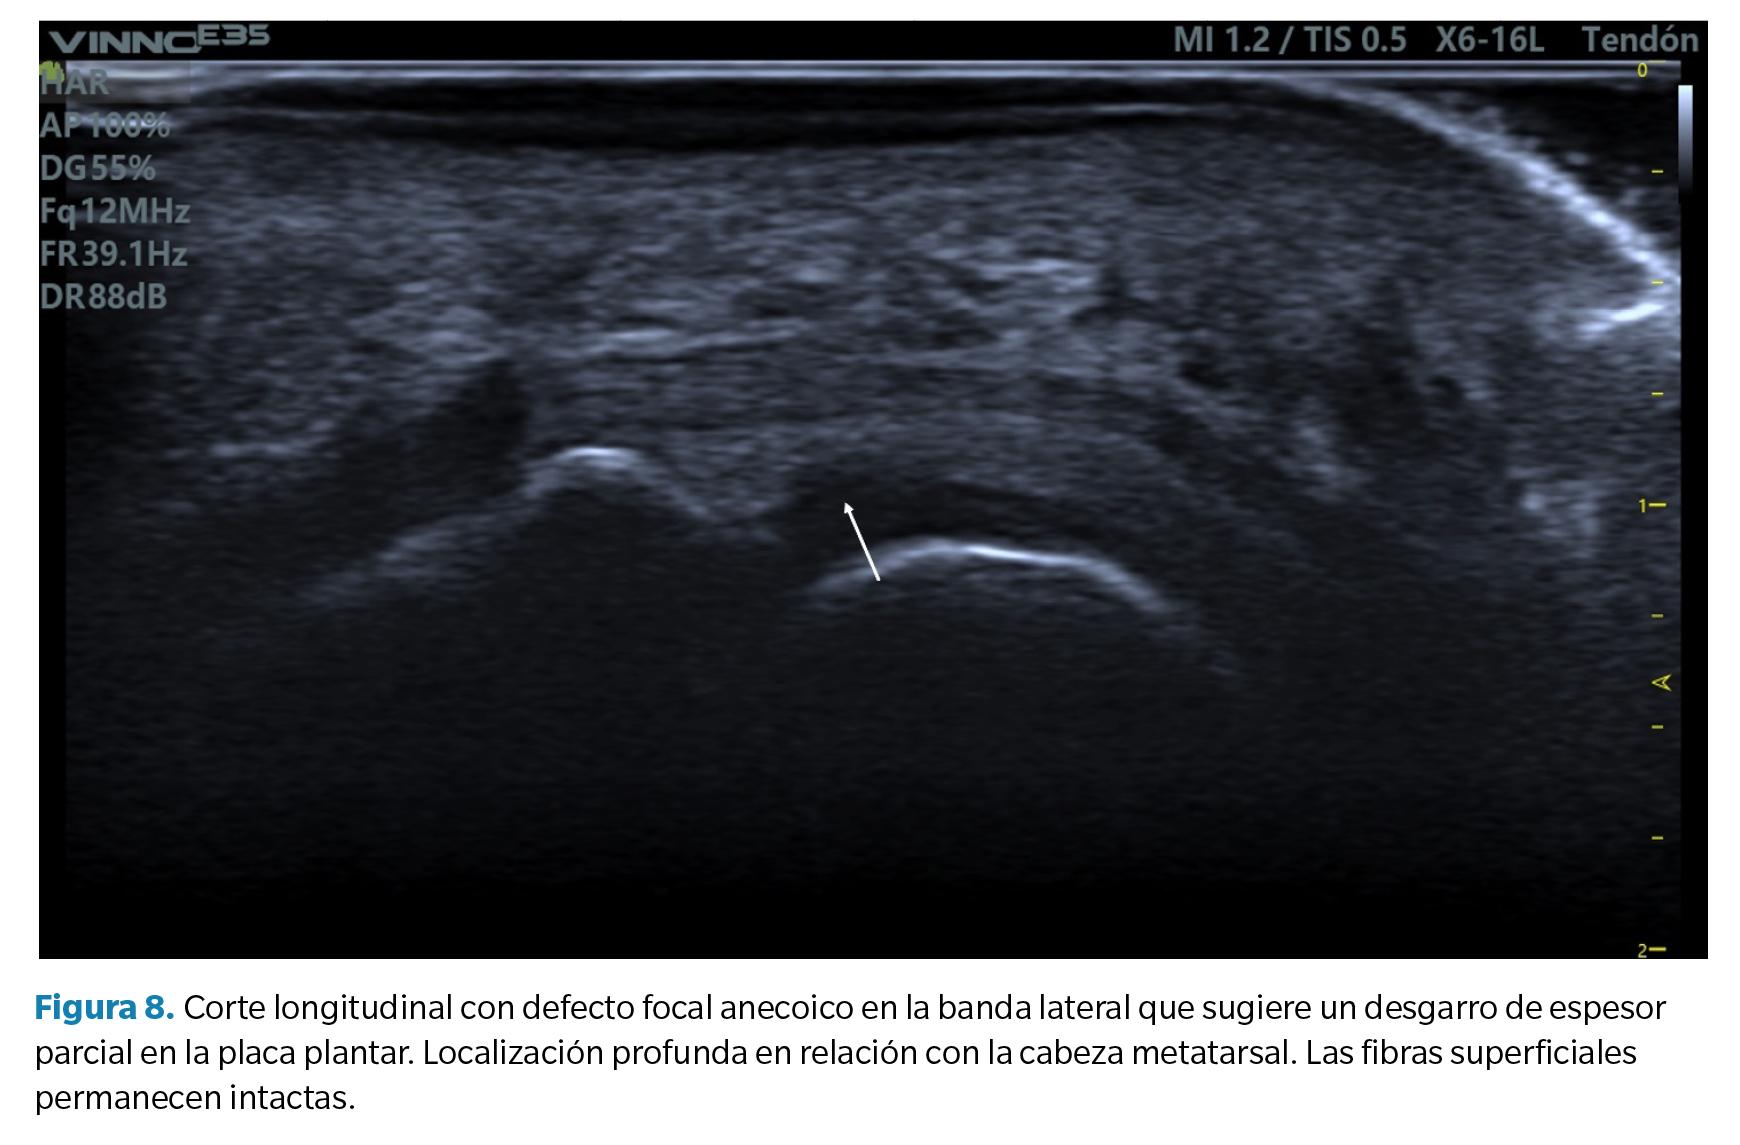

• Corte transverso (eje corto): la placa plantar tendrá una forma curvada que acuna a la cabeza metatarsal. La ecotrama es igualmente granulada, si bien en este corte el aspecto del moteado puede ser más heterogéneo al reflejar la disposición longitudinal de los haces de colágeno. Sobre la placa se revelan los tendones flexores que pueden identificarse fácilmente mediante maniobras de anisotropía (Figura 7).

1. Defecto focal anecoico o hipoecoico. Se aprecian como una hendidura discreta en la zona profunda del tejido (zona que articula con la cabeza metatarsal) en su margen lateral. Cuando las fibras superficiales están intactas hablamos de un desgarro de espesor parcial, mientras que cuando dicho desgarro atraviesa todo el tejido hasta su región superficial hablamos de un desgarro de espesor total39 (Figura 8).